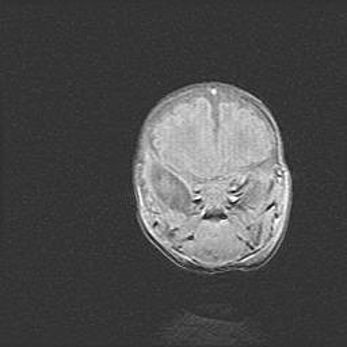

Подострая гематома правой гемисферы мозжечка.

Наружная гидроцефалия.

Возраст: 15 дней

Вес: 3100 г

Пол: женский

Окружность головы: 37 см

Срок гестации: 35-36 недель

При открытой наружной форме гидроцефалии у новорожденных расширяются и переполняются субарахноидные пространства.

Кровоизлияния в мозжечок имеют две клинико-анатомические формы: полушарные гематомы и кровоизлияния в червь.

К появлению этой патологии может привести: повреждения головного мозга, возникающие в результате асфиксии и гипоксии плода при беременности, или травмы во время родов. Редко гематома мозжечка может быть результатом первичной коагулопатии и сосудистой мальформации, диссеминированном внутрисосудистом свертывании, изоиммунной тромбоцитопении.